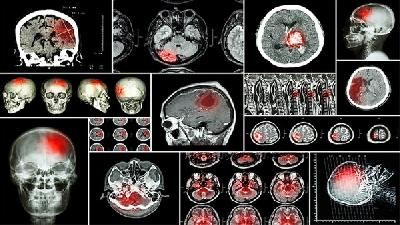

區(qū)分腦癱與發(fā)育遲緩需結(jié)合神經(jīng)影像學(xué)檢查、運(yùn)動(dòng)功能評(píng)估、發(fā)育量表測(cè)試及實(shí)驗(yàn)室檢查等綜合判斷。 1、神經(jīng)影像學(xué): 頭...